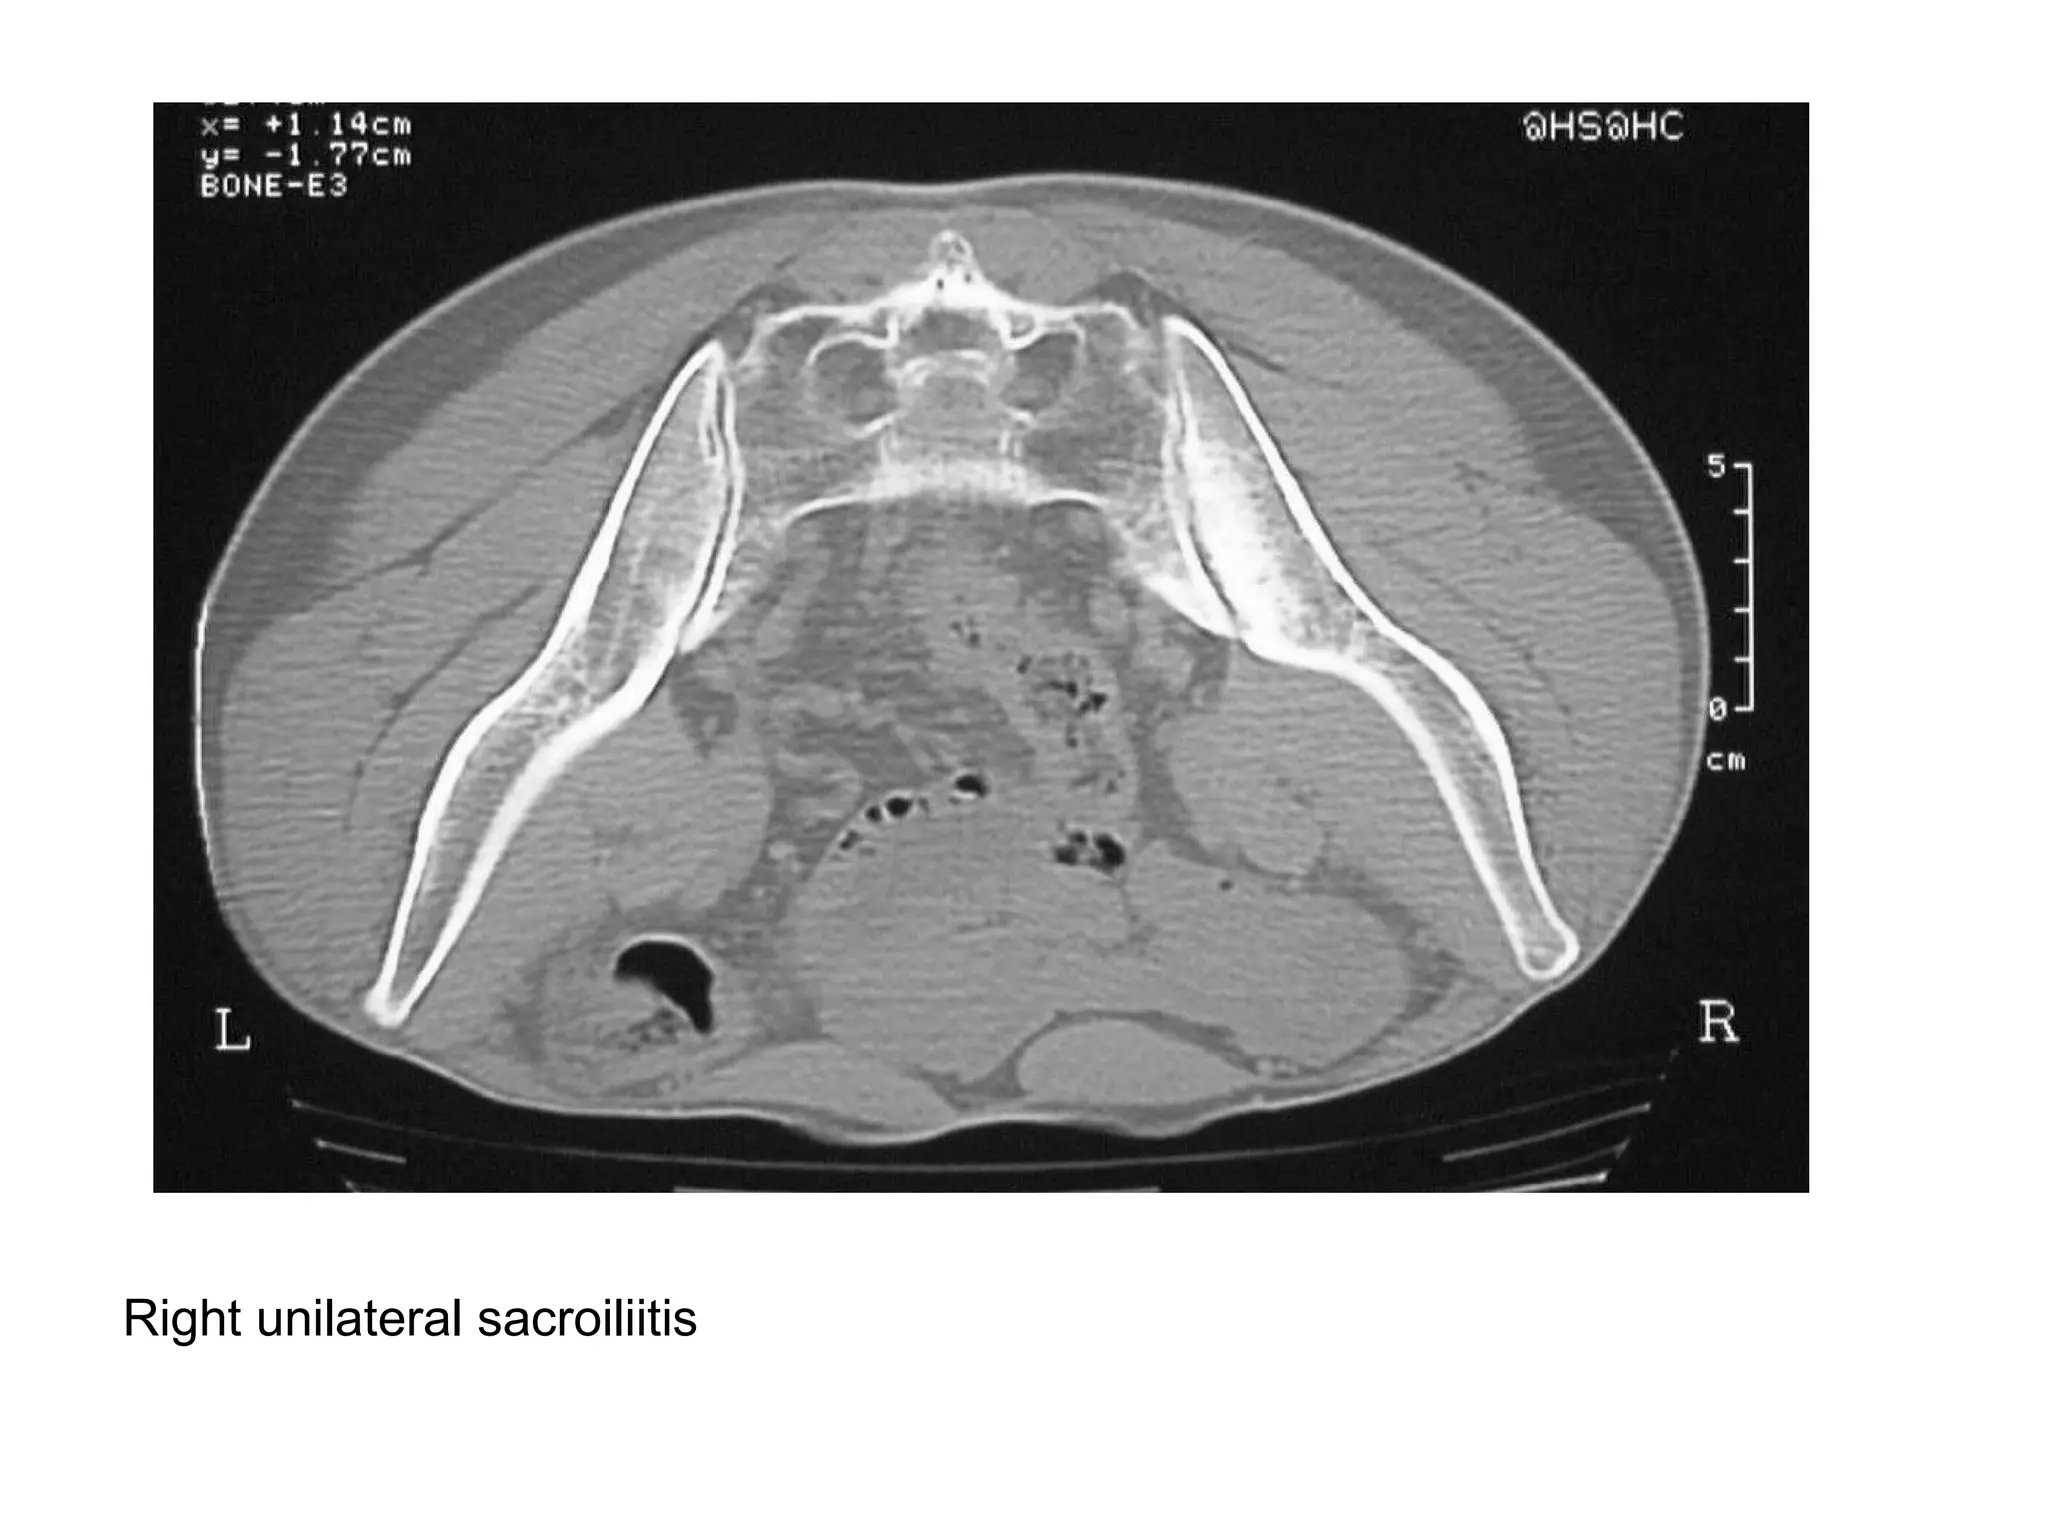

**N.B. : Sacroiliitis is a hallmark of the

spondyloarthritis , symmetric sacroilitis is

caused by IBD & AS , while asymmetric

sacroilitis is caused by psoriatic arthritis and

reactive arthropathy , an important cause of

unilateral sacroilitis is septic arthritis , especially

in an immunocompromised patient or with IV

drug abuse , septic arthritis usually presents with

erosive changes in a patient with fever & SI joint

pain

Bilateral asymmetrical sacroiliitis

Right unilateral sacroiliitis